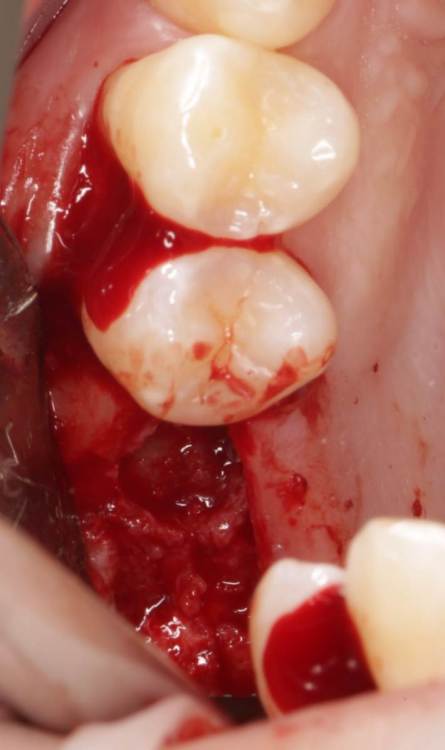

Bier Опубликовано 12 октября, 2021 Поделиться Опубликовано 12 октября, 2021 Как вам синус? В общем подумал я подумал, и крестально его открыл 6 Ссылка на комментарий

Bier Опубликовано 12 октября, 2021 Автор Поделиться Опубликовано 12 октября, 2021 5 часов назад, Raystom сказал: Bier, мембрана была или так ушились? стимул-осс положил 1 Ссылка на комментарий

Bier Опубликовано 12 октября, 2021 Автор Поделиться Опубликовано 12 октября, 2021 25 минут назад, Карен Аванесов сказал: Ну как тебе сказать Олег? Видно ты старался, "дырочка" маленькая, времени наверно много потратил. Лучше расскажи про тот имплантат который как бы вне фокуса и вне кости, про его роль в этой работе? там синус на сгустке Ссылка на комментарий

Bier Опубликовано 13 октября, 2021 Автор Поделиться Опубликовано 13 октября, 2021 1 час назад, Карен Аванесов сказал: А ты азартен! несколько сомнительная инвестиция в сгусток, и даже если этот твой кейс готов) Почему? я 99% закрытых синусов делаю на сгустке сегодня. до 5мм включительно - ничего в пазуху не пихаю. 3 1 Ссылка на комментарий